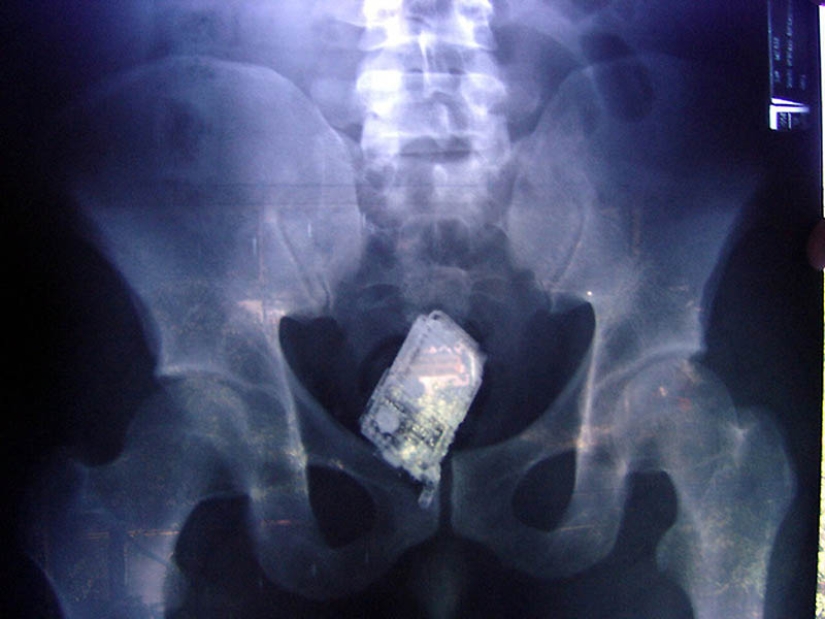

14. Teléfono móvil en los intestinos del prisionero.